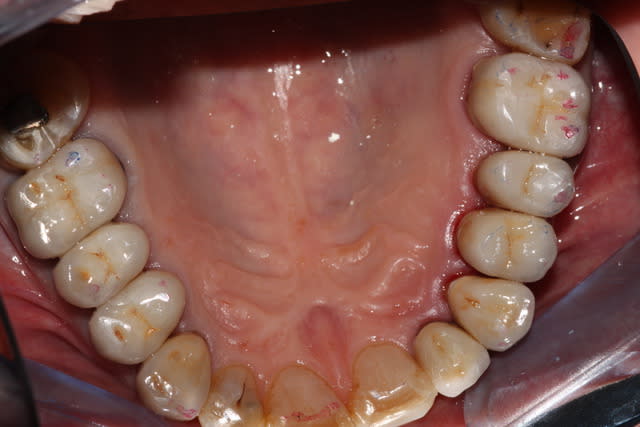

Voici un petit cas du jour sans prétention, un patient content ce soir, et moi aussi.

Modestecasdujour2 v3zhut - Eugenol

Modestecasdujour1 dthezj - Eugenol